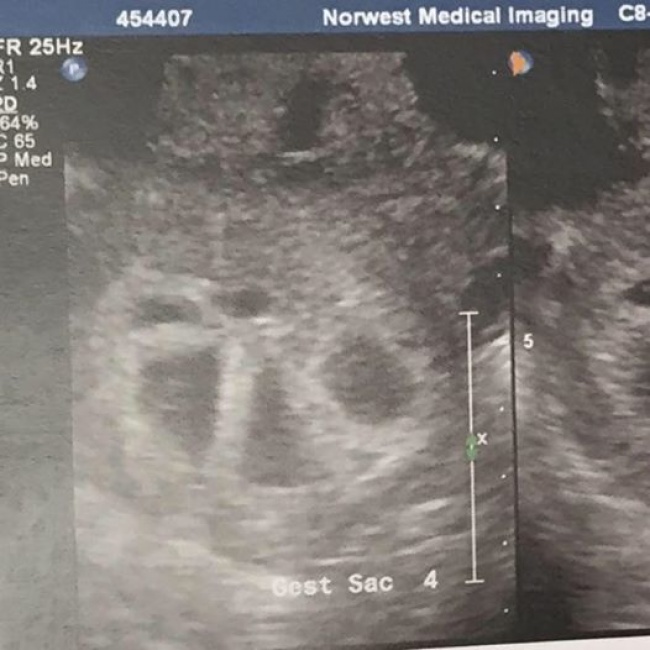

интересноеугадайте, что это за чесночок на УЗИ?

Это пятерняшки! А так выглядит их беременная мама